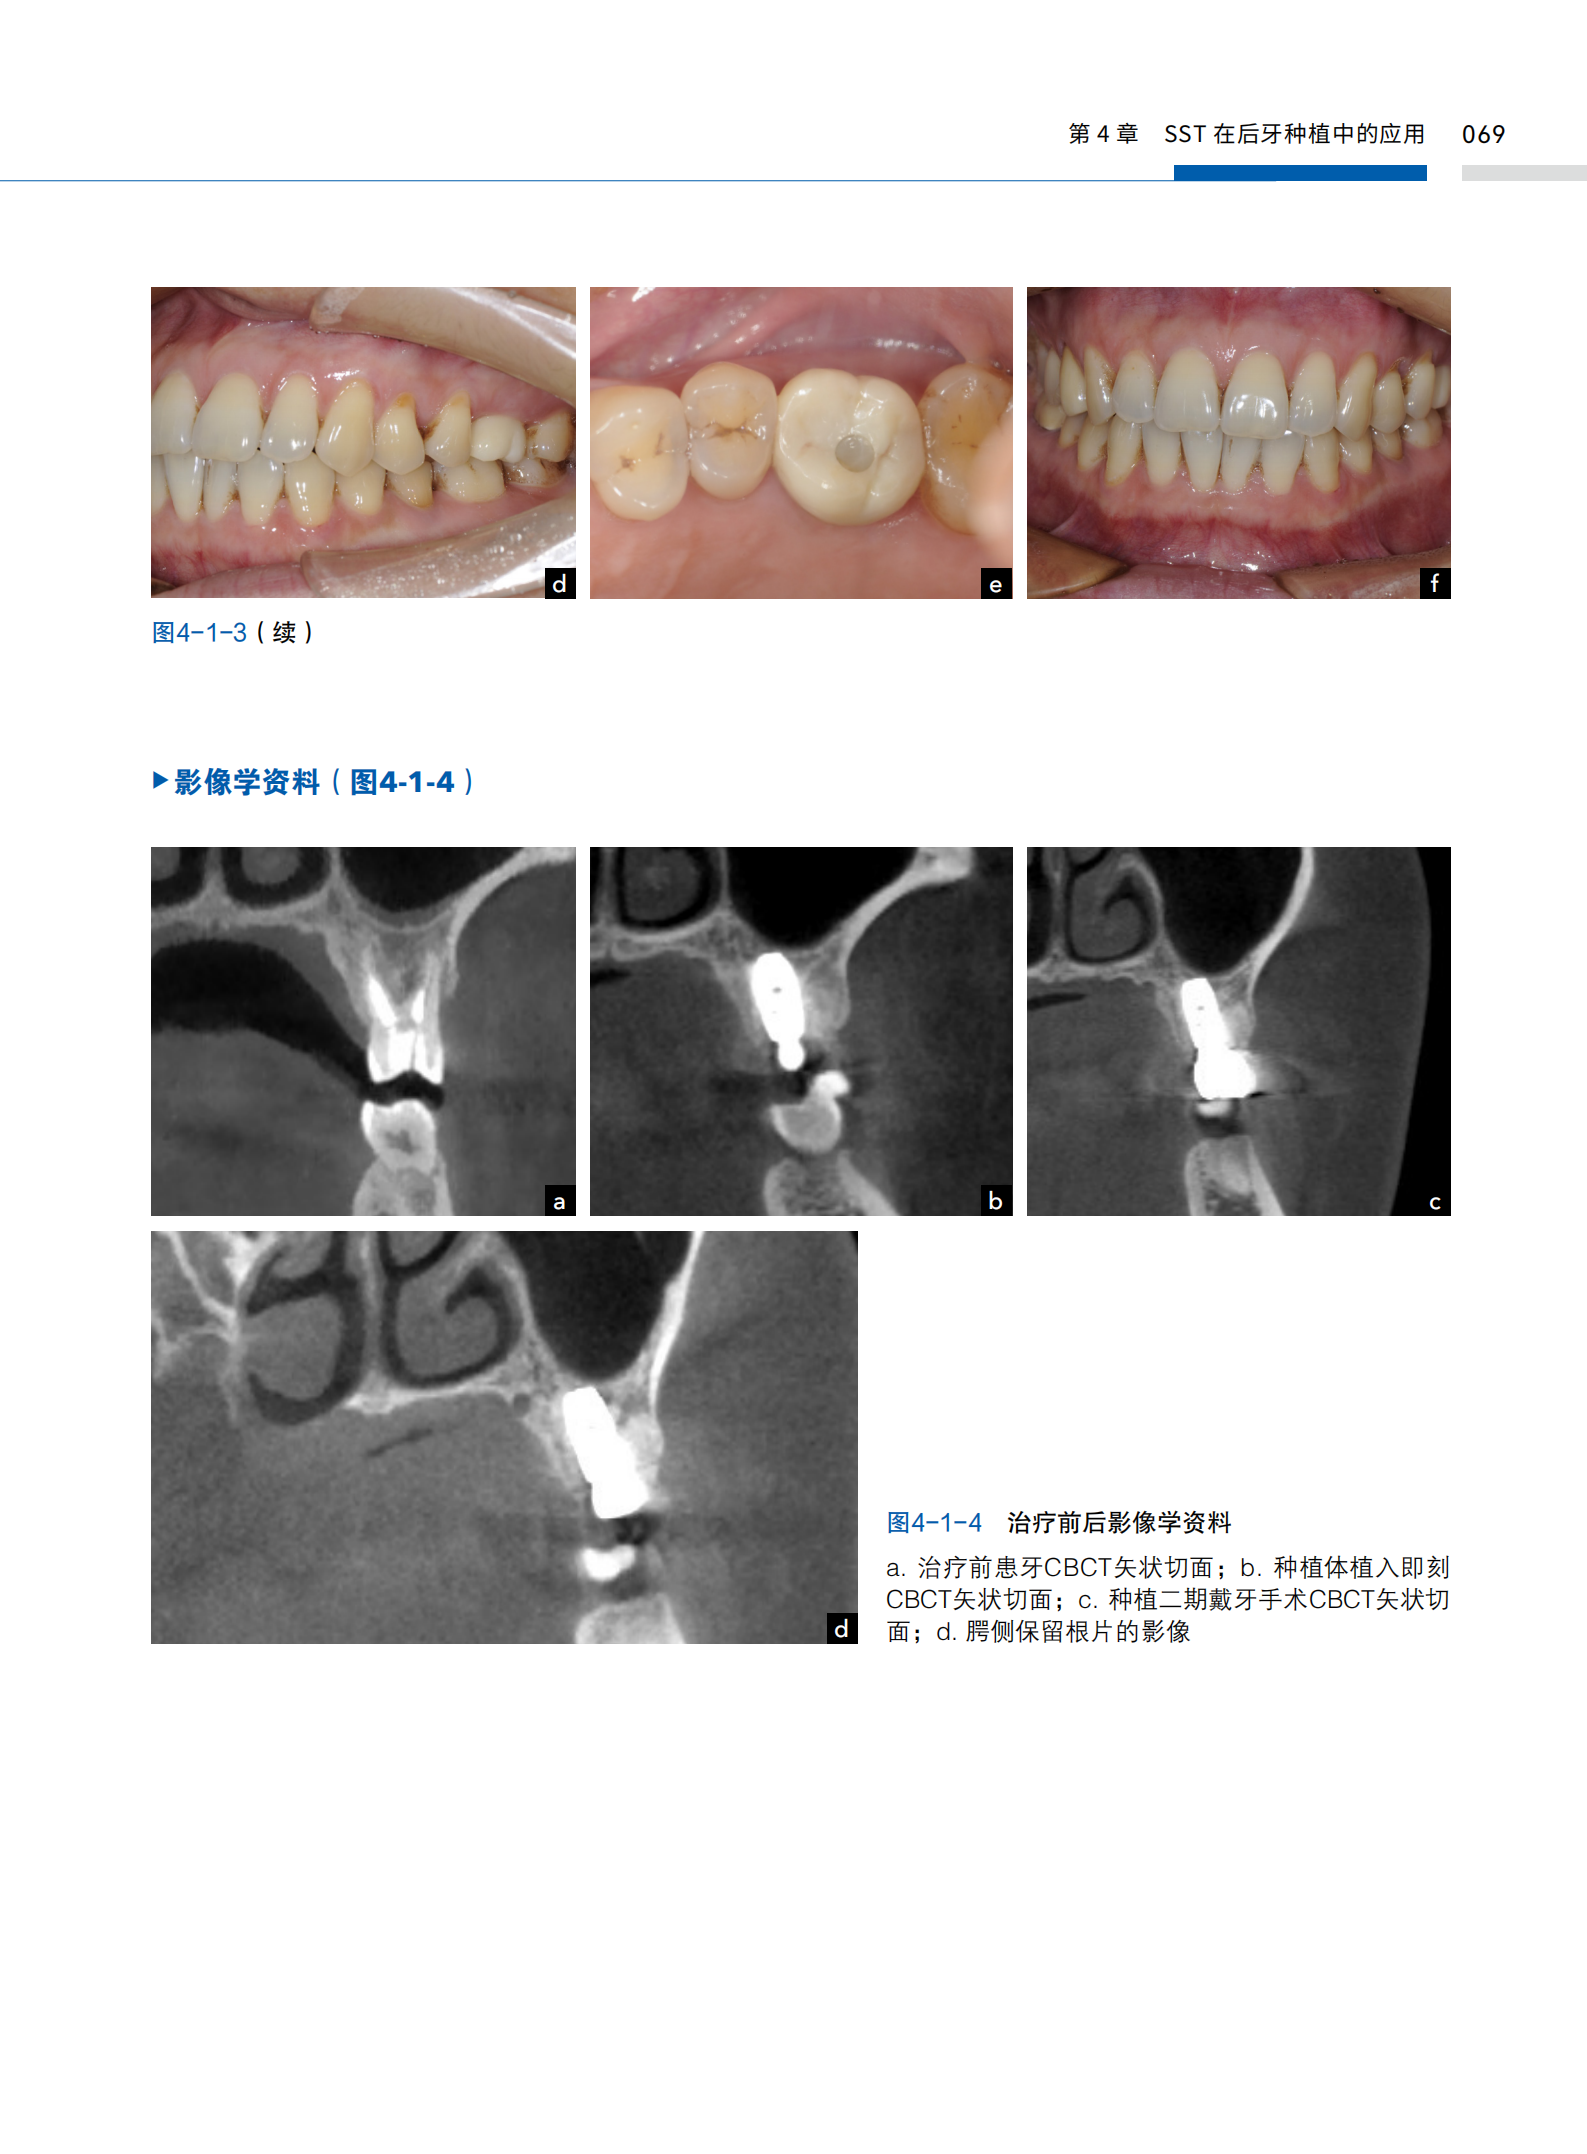

本書由中山大學光華口腔醫學院附屬口腔醫院王勁茗教授和鄧飛龍教授團隊傾力打造,系統介紹了根盾科技(socket shield technique,SST)在前牙區、後牙區以及全口無牙頜種植修復中的應用。 從科技原理到臨床實戰,從術前評估到術後管理,書中不僅詳細闡述了SST的適應證、操作流程和併發症處理,還通過大量真實病例展示了其卓越的臨床效果。